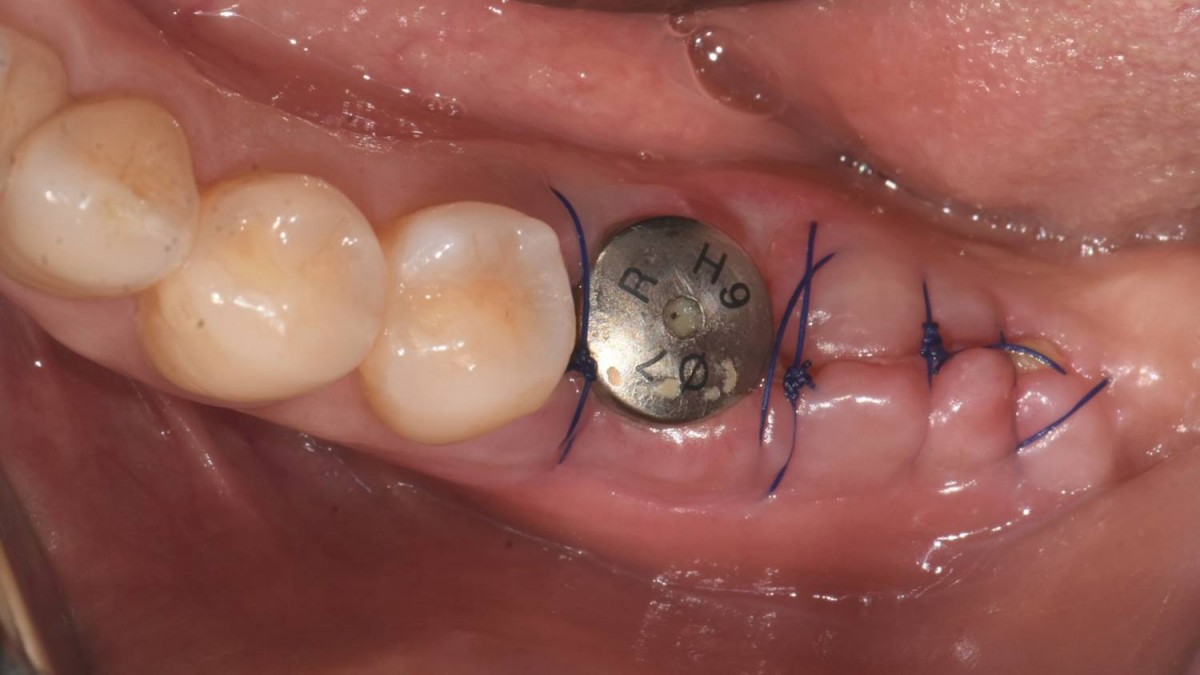

It was decided to proceed with implant-supported restoration in the left molar part first.

▲post-op panoramic radiograph.